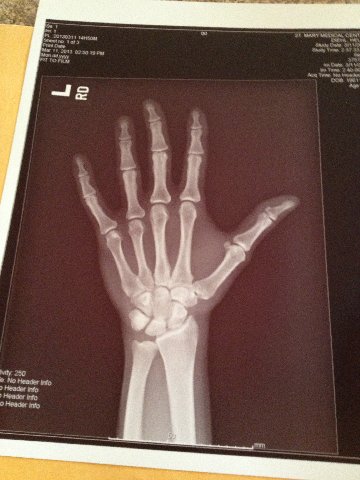

Had to go to the Doctor today because I

developed this condition called Trigger Thumb.it’s the same as trigger finger –

but my thumb instead.

learn about it here: |

I had to go to the hospital to get an

X-ray of my hand. I have an appointment Friday

with an Orthopedic Surgeon to get an assessment. |